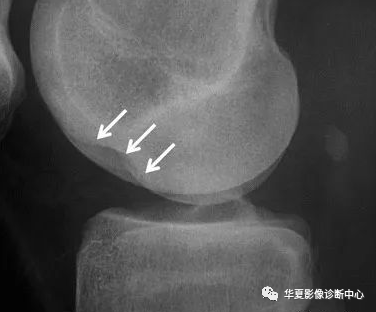

股骨外侧髁“深沟”征(Lateral femoral “notch” sign)

1-髌上囊积液、2-股骨外侧髁深沟征、3-后外侧胫骨平台损伤,共同征像表明轴移损伤机制